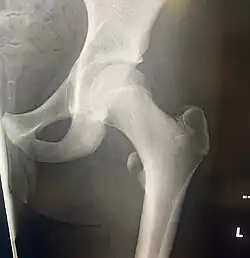

![]() Left hip-joint, opened by removing the floor of the acetabulum from within the pelvis. | |